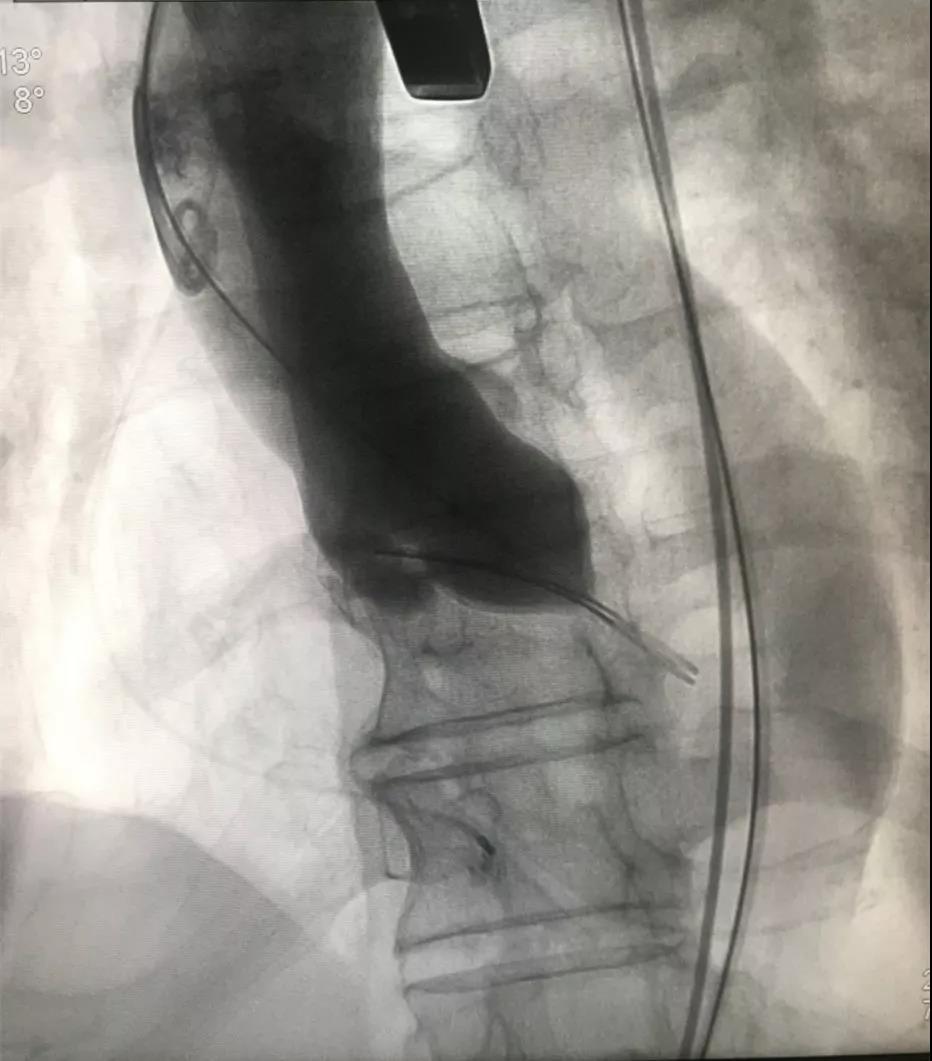

▲主动脉瓣球囊扩张